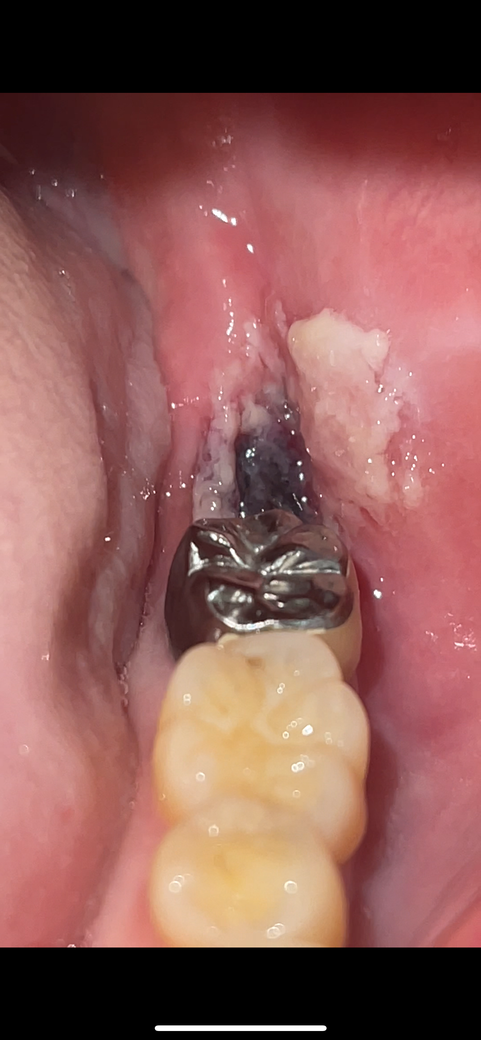

사랑니 4일차 혈병이 떨어지려는 것처럼 보이는데 괜찮나요?

사랑니 발치 4일차인데 뿌리가 안쪽 ㄱ자로 휘어진 기형인 사랑니를 발치했습니다.

크게 고생할거라 하셨지만 지혈은 8시간이 돼서야 되었지만 그래도 큰 고통없이 혈병이 형성됐습니다

그런데 3일차부터 호빵,자장면 등 일반식을 섭취하기 시작했는데

4일차인 오늘 혈병 쪽에 욱씬거리는 통증과 함께 떨어지려는 것처럼 보이는 현재 상태가 되었습니다

• 1번 째 사진